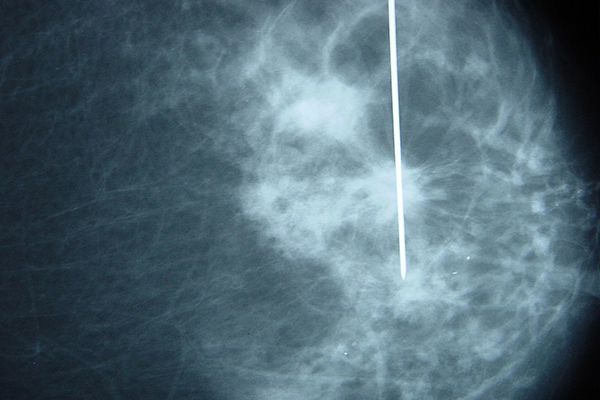

O dia em que me colocaram o arpão 🚑

A biópsia: dor, espera e um abraço 😭

Um pouco antes das 10h, cheguei para fazer o exame que iria, muito provavelmente, definir os próximos meses ou... Ler mais

17/03/2025

A biópsia, os exames e o peso da espera 🩻